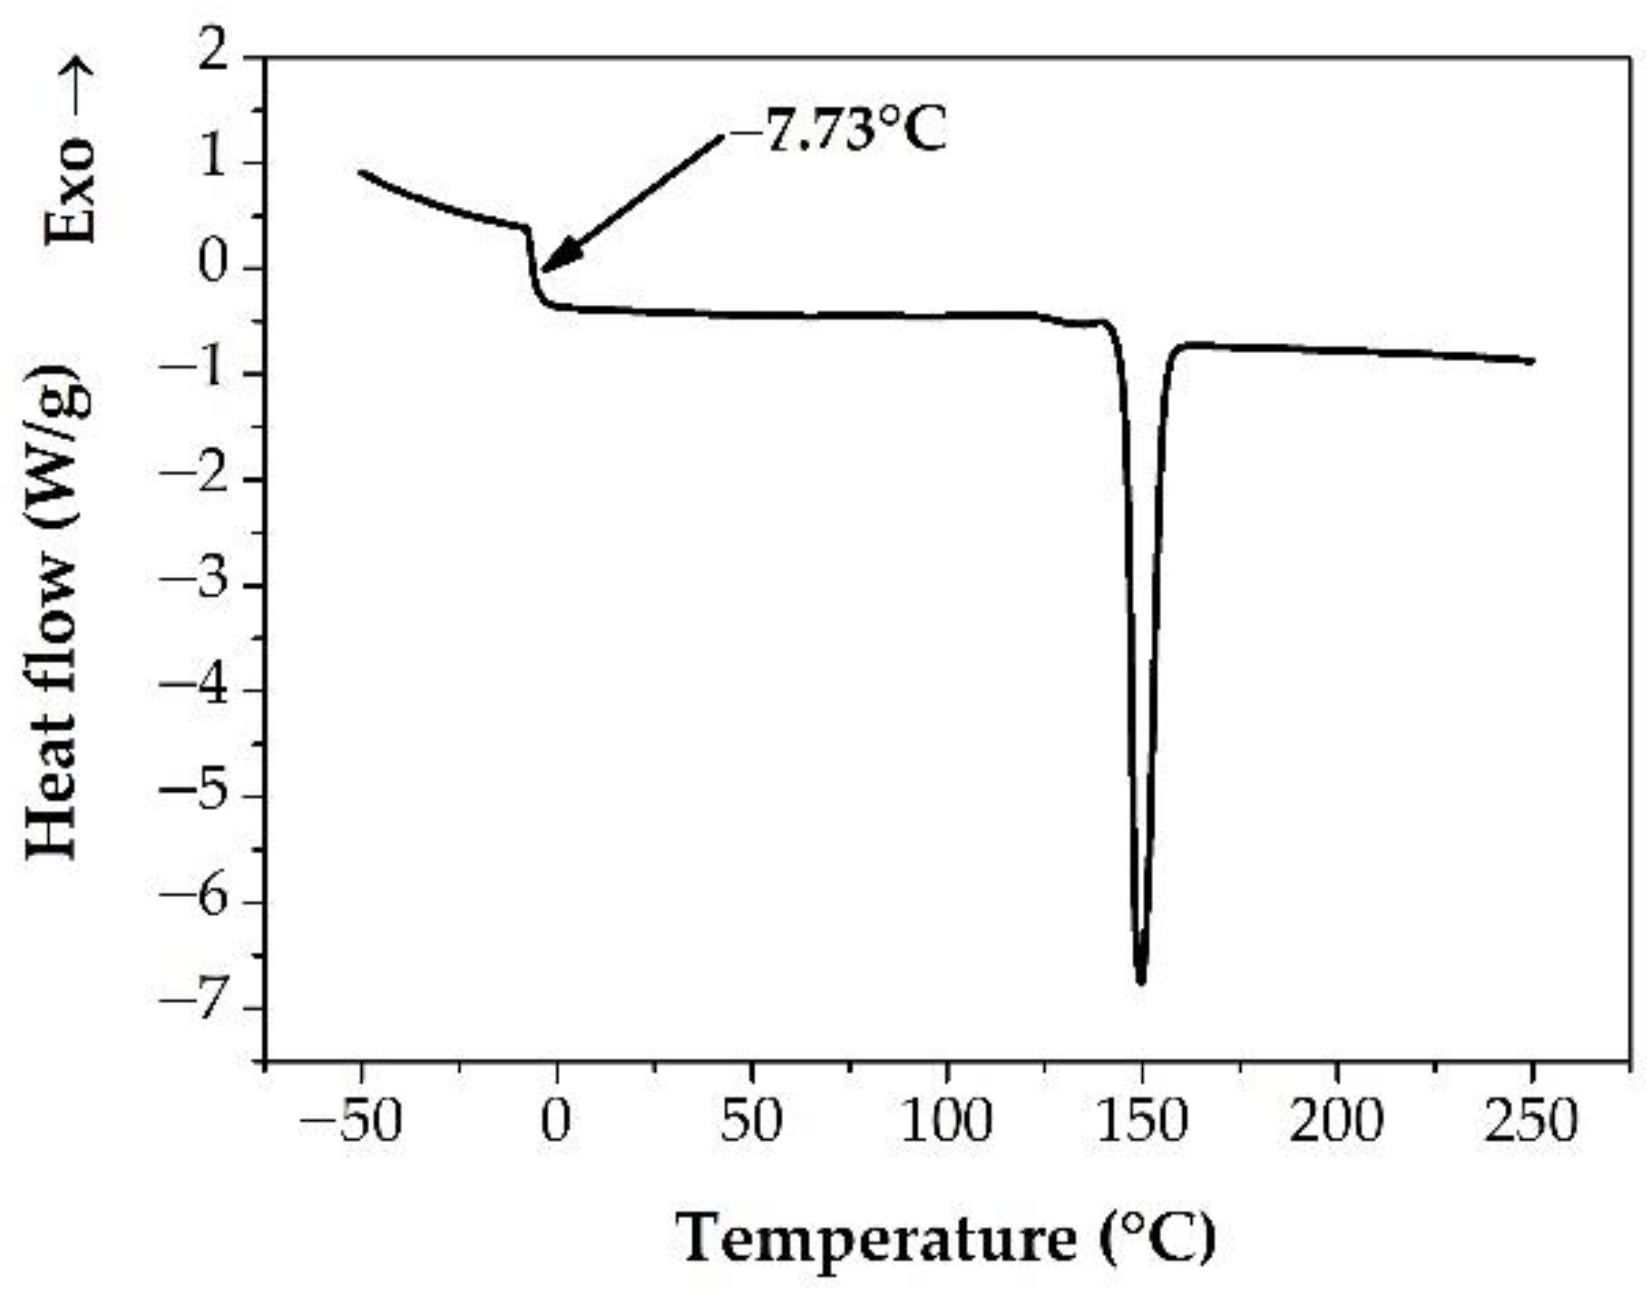

3.1. Preparation and Basic Characterization of the Samples

3.2. Measuring the Glass Transition Temperature with Different Methods